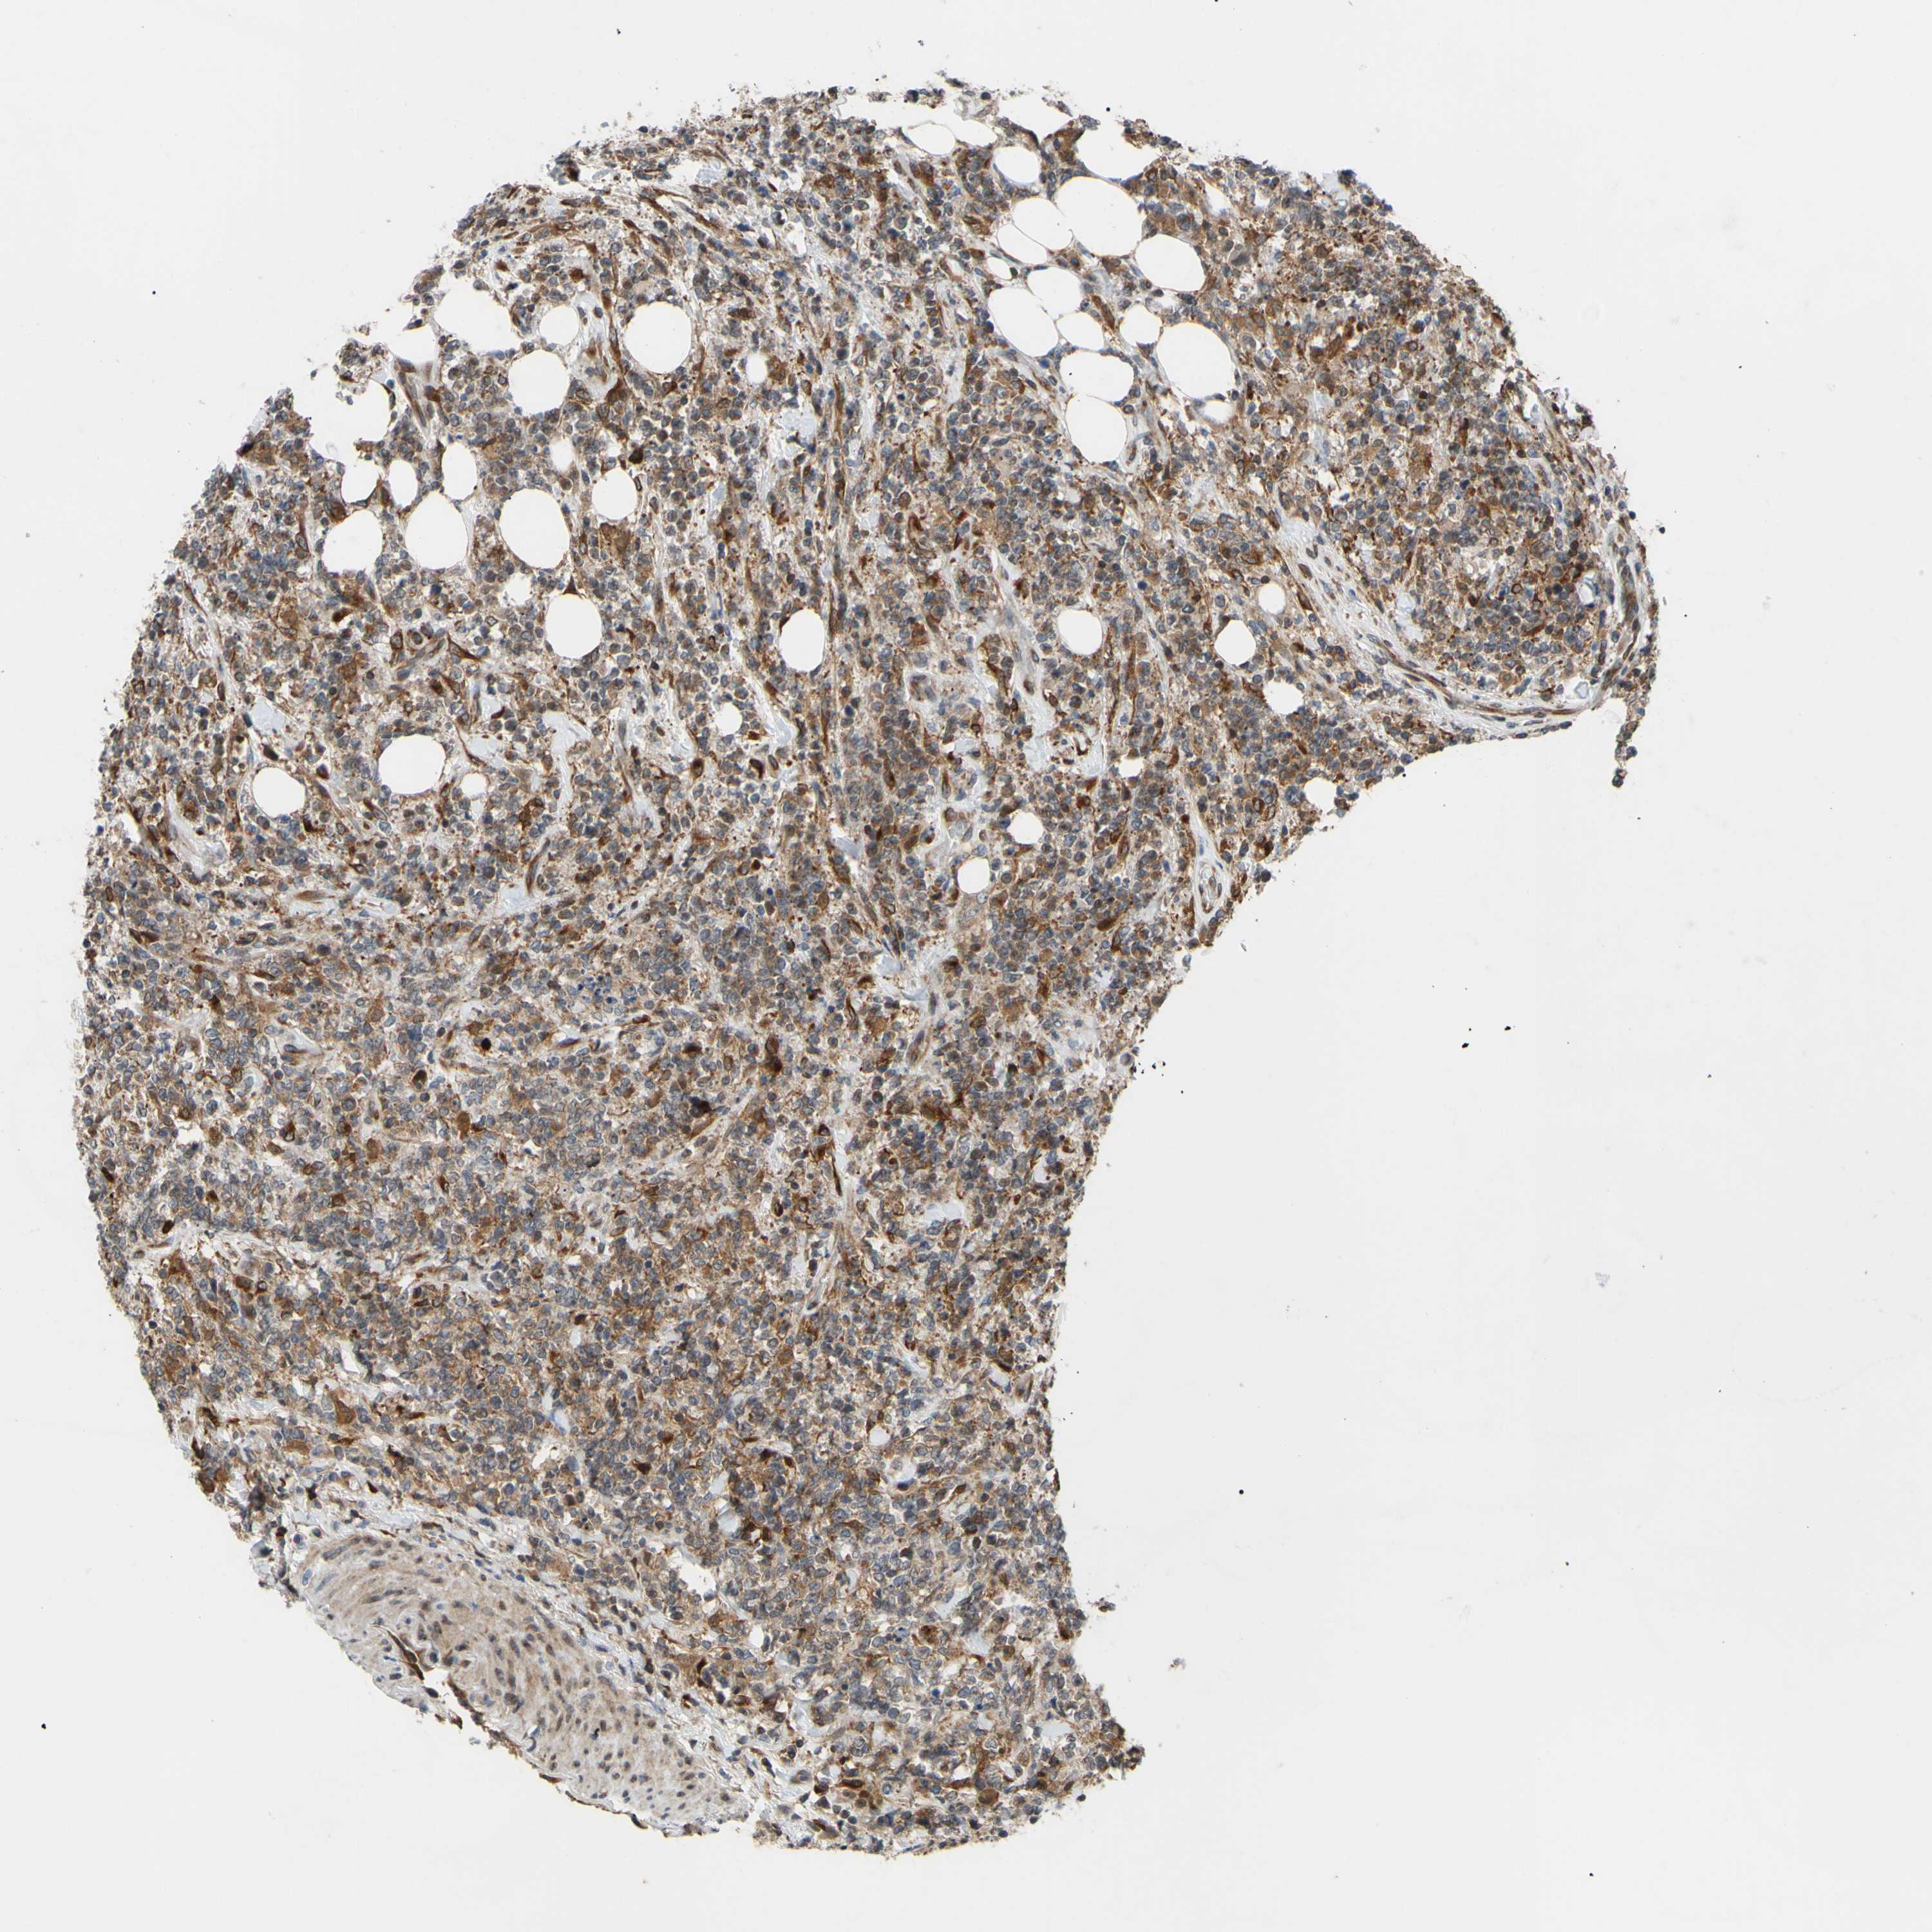

LYMPHOMA - Protein expressioni

A mouse-over function shows sample information and annotation data. Click on an image to view it in a full screen mode. Samples can be filtered based on level of antibody staining by selecting one or several of the following categories: high, medium, low and not detected. The assay and annotation is described here.

Antibody stainingi

Antibody staining in the annotated cell types in the current human tissue is reported as not detected, low, medium, or high, based on conventional immunohistochemistry profiling in selected tissues. This score is based on the combination of the staining intensity and fraction of stained cells.

Each image is clickable and will lead to virtual microscopy that enables deeper exploration of all samples and also displays staining intensity scores, fraction scores and subcellular localization as well as patient and tissue information for each sample.

Antibody HPA002859

Malignant lymphoma, non-Hodgkin's type, High grade

Malignant lymphoma, non-Hodgkin's type, Low grade

Hodgkin's disease, NOS